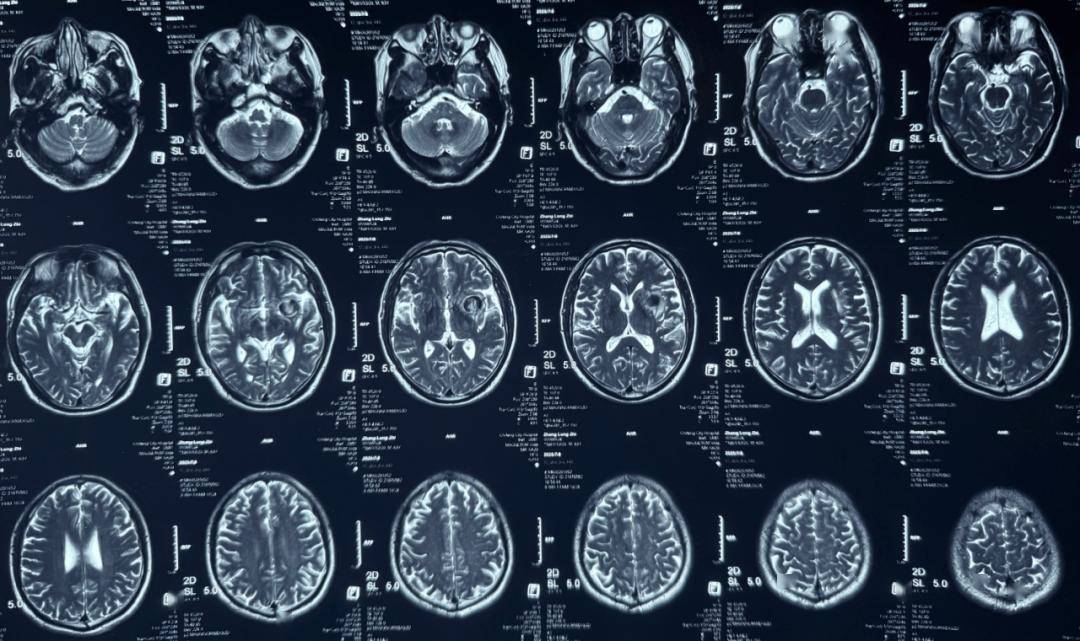

术前影像

术前正位DSA

术前侧位DSA

术前核磁